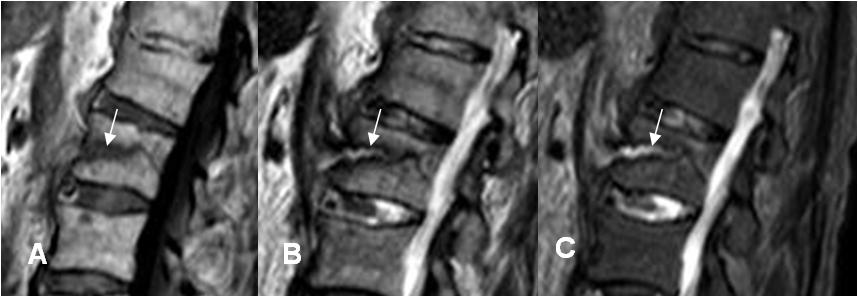

Fig 207 B. Fractura de Chance.

A: RM sagital en T1, B: RM sagital en T2 y C: RM sagital en STIR.. Igual paciente anterior. Fractura en sentido transverso, que compromete el cuerpo de L1. No existe fragmento retropulsado, ni compromiso del complejo ligamentario posterior.